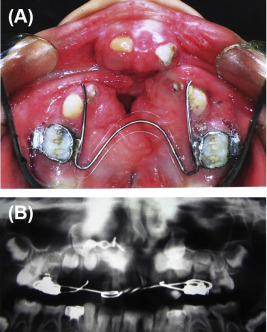

(A) Protruded premaxilla. (B) Cropped orthopantomograph (OPG) after premaxillary ...

Figure 4.

(A) Protruded premaxilla. (B) Cropped orthopantomograph (OPG) after premaxillary osteotomy and bone grafting.

The patient was an 8-year-old boy with unsightly protruded premaxilla. He had experienced an unsuccessful tongue flap for the closure of a large palatal fistula. It was managed like the other two cases presented above (Figure 4). This patient was followed up for 1 year.